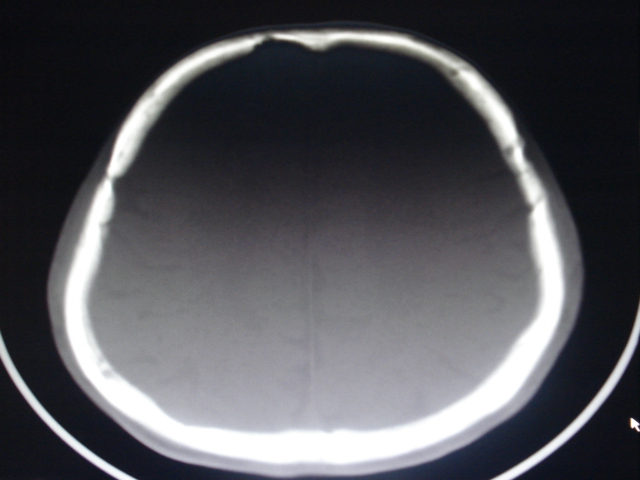

男性,48岁。发现右顶部包块一月余,质软有轻压痛。

其余没问题的层面我没有发上来,请教各位老师,可以考虑嗜酸性肉芽肿吗?

骨质破坏+软组织肿块+好发部位  支持骨嗜酸性肉芽肿。

可以考虑为骨嗜酸性肉芽肿,但是必须和骨髓炎、结核、孤立性骨囊肿、纤维异样增殖症和一些恶性骨肿瘤相鉴别。故应作活组织检查以确诊。

年龄大,无“纽扣样”死骨,软组织肿块密度较低且边界清楚,由内板向外破坏,不支持嗜酸性肉芽肿。

考虑转移瘤、表皮样囊肿、骨纤、板障型脑膜瘤、颅骨淋巴瘤鉴别。

倾向于板障型脑膜瘤,淋巴瘤待排除,建议增强及mri进一步检查。